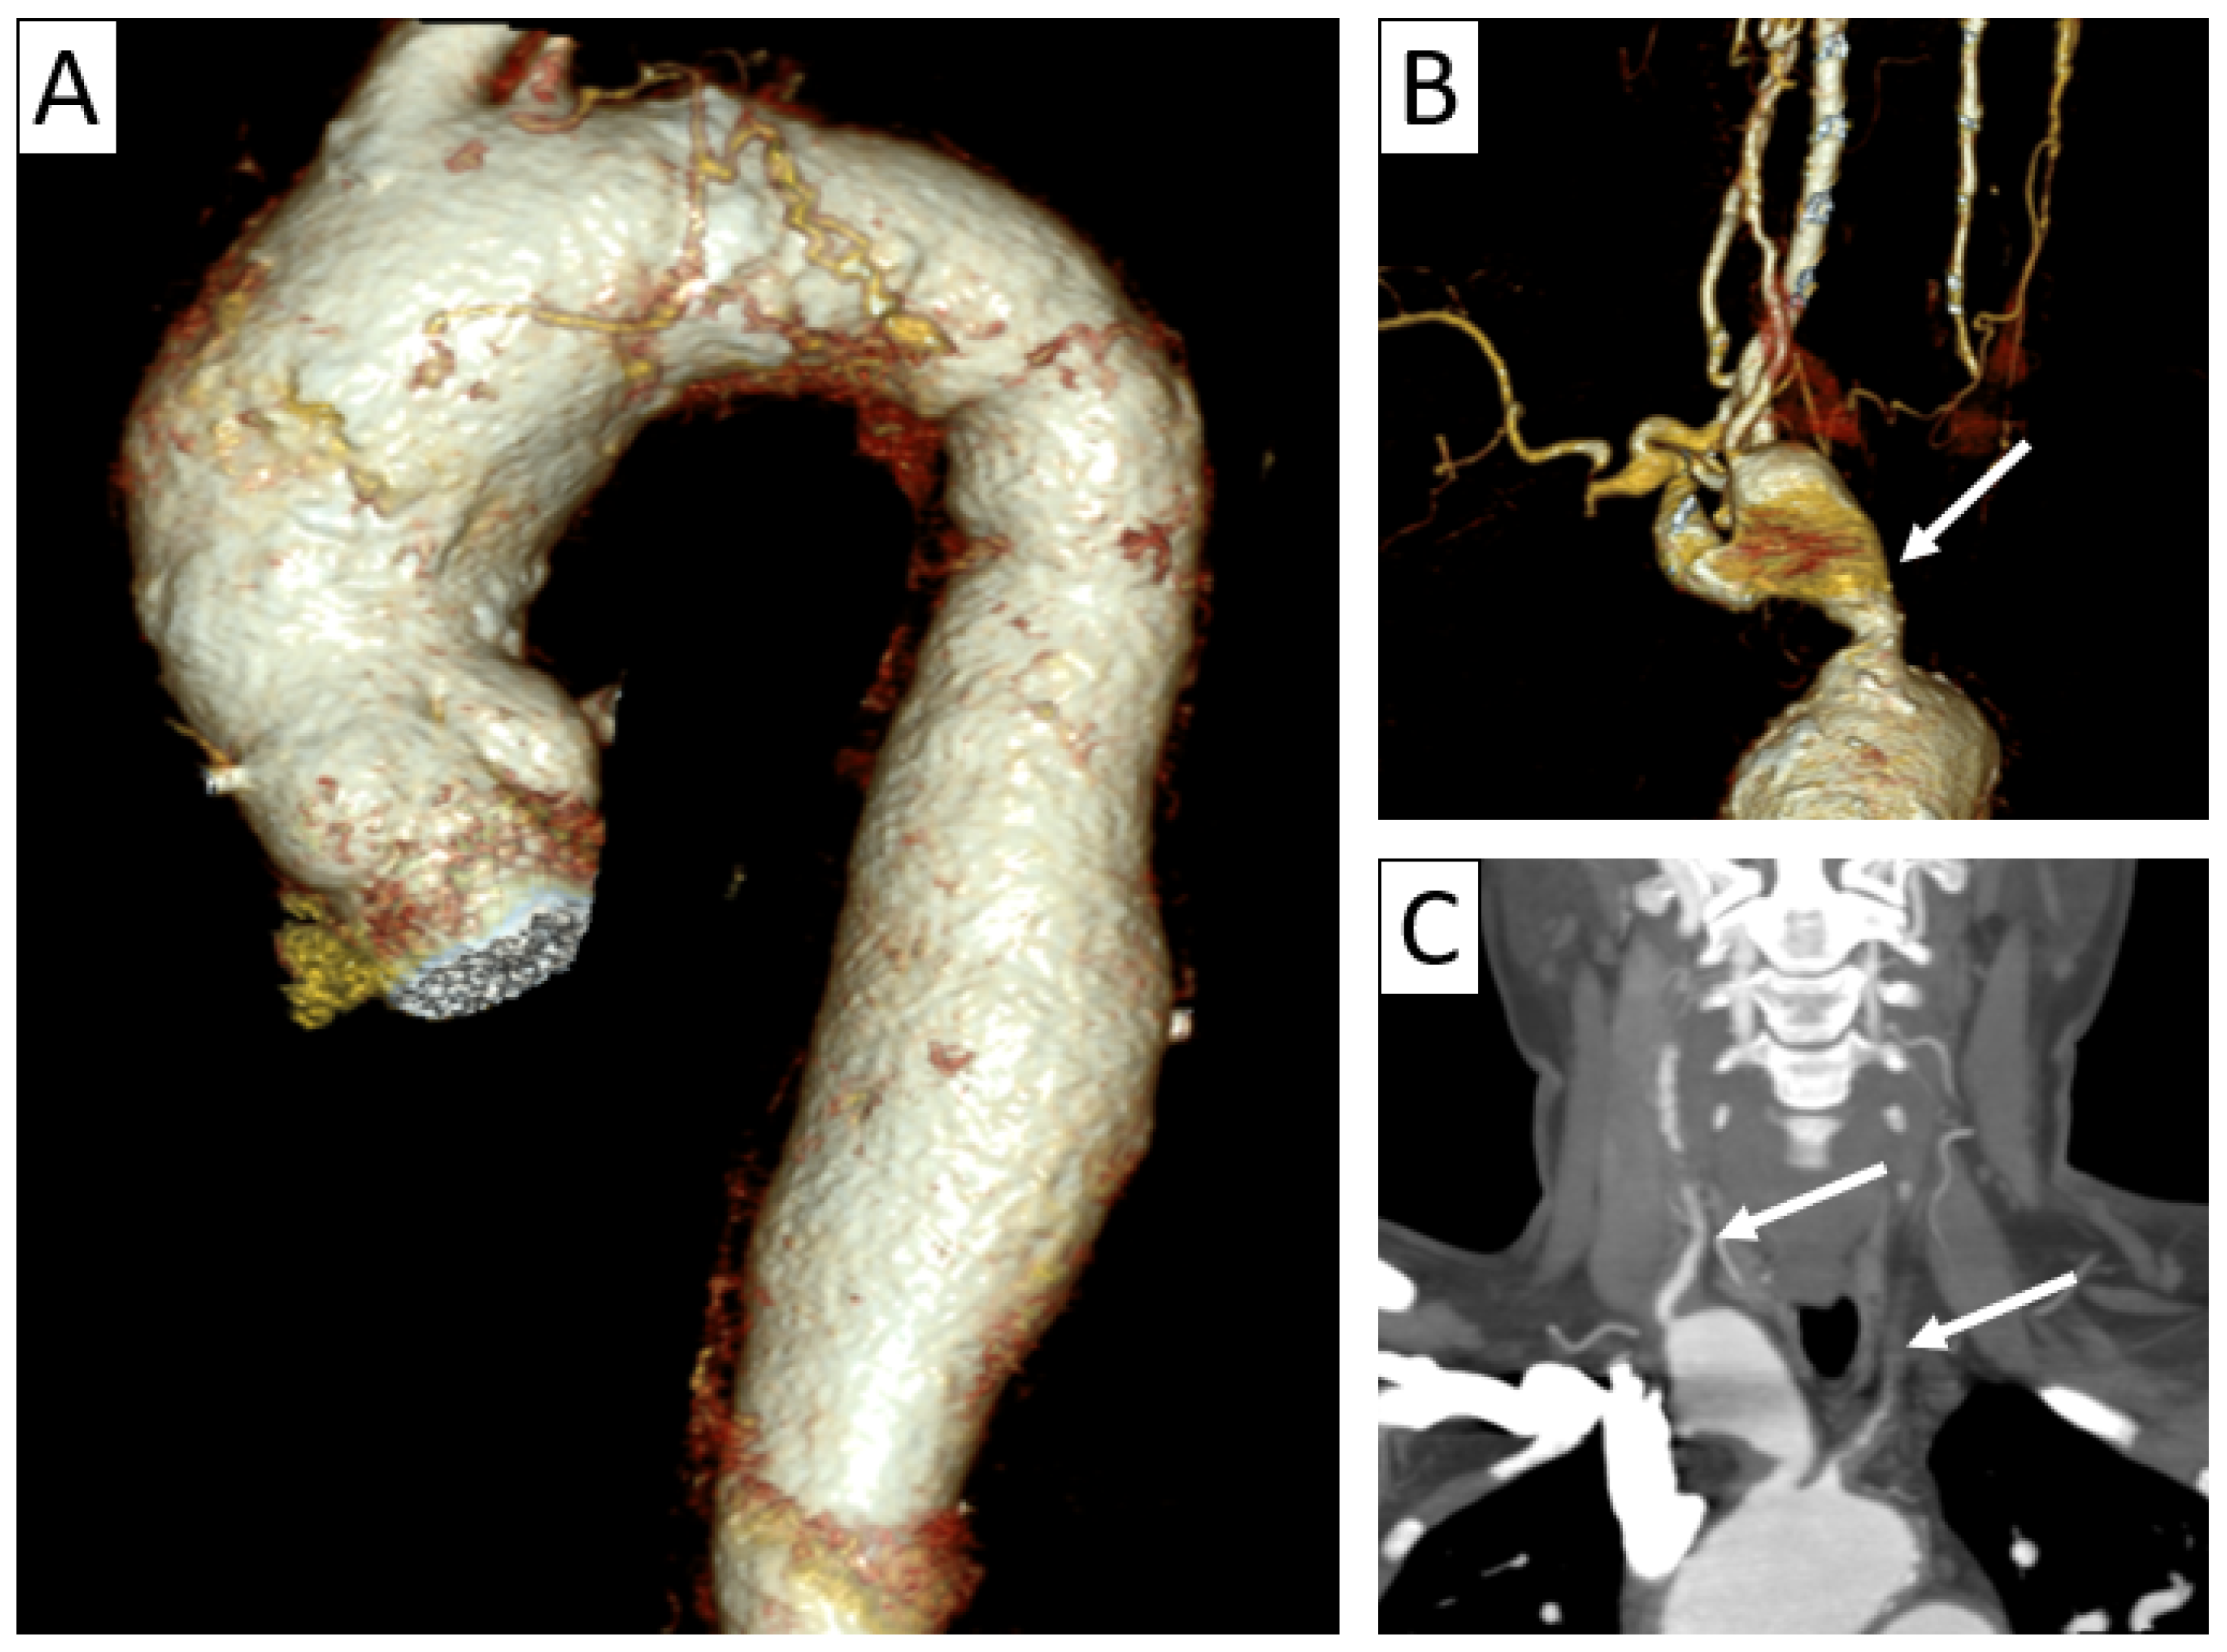

6.2.2. Takayasu Arteritis

| CTA | Circumferential parietal thickening Vessel wall enhancement | Circumferential parietal thickening Vessel wall enhancement Luminal stenosis or narrowing |